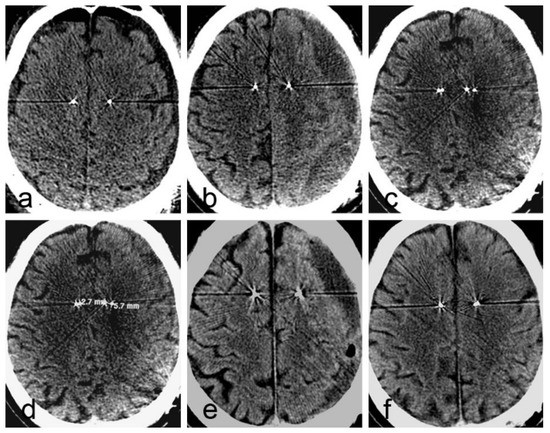

2.1. Case 1

| Case 1 | 62 | F | Parkison’s disease | GPI | Yes | Yes | 36 days | description | poor |